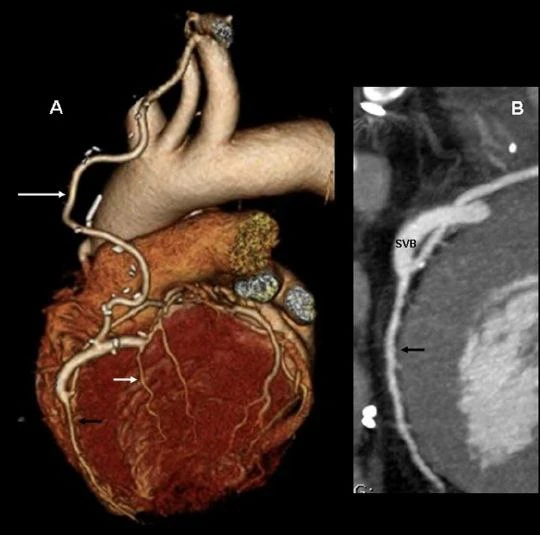

КТ-коронарография является высокоинформативным методом диагностики, позволяющим оценить состояние сердца и коронарных артерий. Исследование проводится с использованием мультиспирального компьютерного томографа с контрастированием сосудов.

Во время процедуры пациенту вводится контрастное вещество, благодаря которому становится возможной точная визуализация сосудов сердца и выявление потенциальных сужений или блокировок кровотока.

- оценка эффективности лечения или состояния коронарных шунтов;